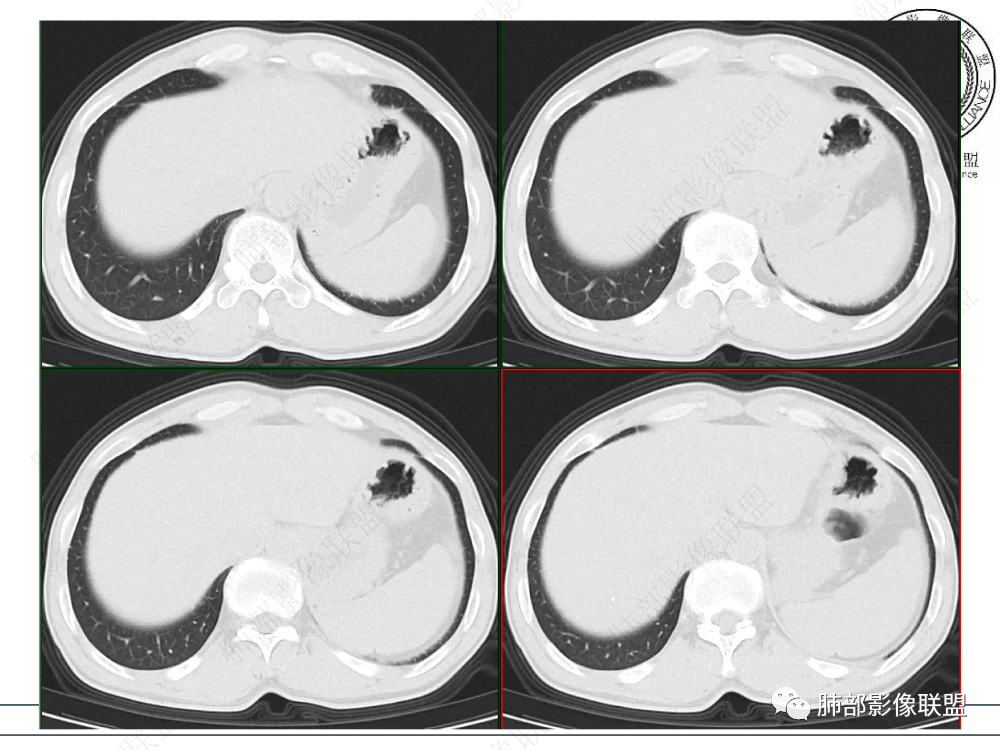

1.临床资料:中老年男性,病史较长-8个月,主诉胸痛,实验室资料:乳酸脱氢酶(LDH)升高。

2.影像表现:前上纵隔较大肿块,密度不均,形态不规则,边界不清,有结节样突起,脂肪间隙显示不清。病灶侵犯左无名静脉及上腔静脉,其中左无名静脉闭塞(胸背部侧支循环明显,亦表明回流受阻)。增强后轻中度不均强化。坏死边界欠清晰。可见心包积液,提示心包受侵犯。右侧上叶及纵隔胸膜下结节影,疑胸膜肺转移可能。胸骨柄后缘皮质不完整,疑骨质破坏(未提供骨窗及矢状位图像)。左锁骨上可见肿大淋巴结。

胸腺癌:病灶边界不清,骨骼及血管受侵破坏,胸膜、肺及心包受侵转移等首先想到胸腺癌。胸腺癌最常见病理类型为鳞癌,占70-79%。预后较差,50-65%初诊时伴肺转移,极少伴重症肌无力。影像:胸腺鳞癌形态不规则,易坏死,范围大,坏死区边缘常模糊。

胸腺瘤:胸腺瘤大多边界较清楚。边界模糊或心包侵犯可见于B3型胸腺瘤和癌,但胸腺瘤罕见远处转移、淋巴结转移和纵隔大血管侵犯。

淋巴瘤:体积常较大,常见常在10cm以上,相对低密度结节样堆砌感比较明显,对待骨骼、血管等结构相对“温和”,所谓“血管漂浮”、“肉包骨”则较为常见。病理类型几乎只见于:经典HD、大B细胞淋巴瘤,前驱T淋巴母细胞瘤。实验室检查LDH可升高。初诊时罕见钙化,罕见胸膜受侵。有坏死也常常边界清楚或呈囊变样外观,可伴纵隔、锁骨上淋巴结肿大。